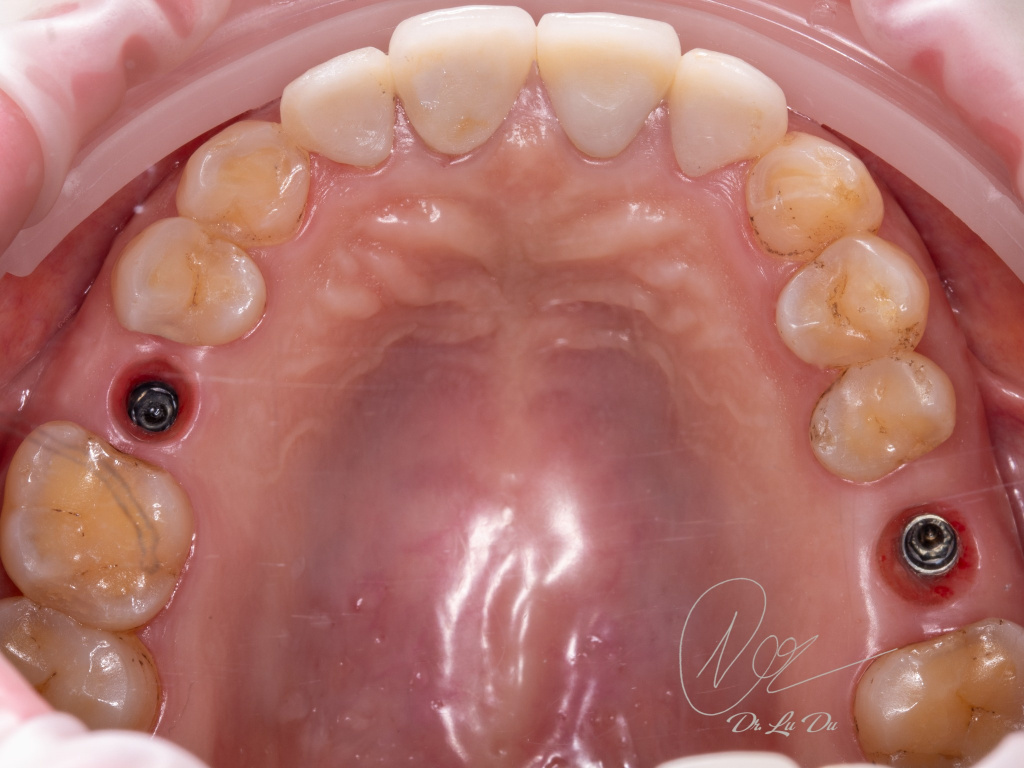

Имплантация AnyRidge с двусторонним закрытым синус-лифтингом.

Осложнения: правосторонний гайморит.